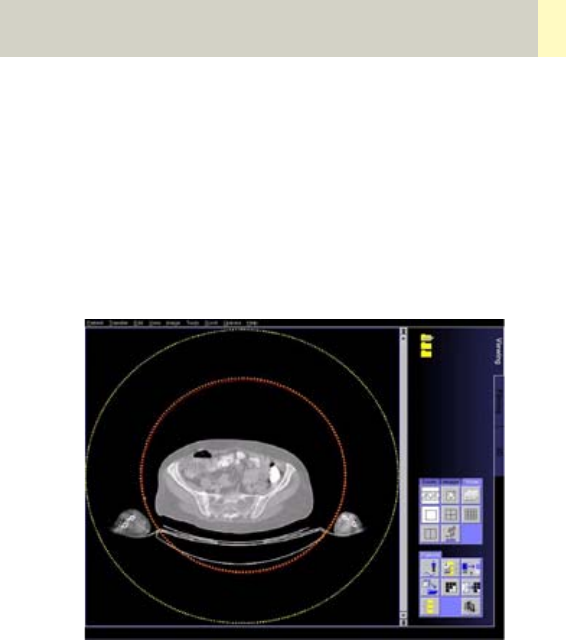

•Radiation Therapy Planning 462

•Workflow 468

•Scan Protocols 470

- Overview 470

- RT_Head 472

- RT_Thorax 474

- RT_Breast 476

- RT_Abdomen 478

- RT_Pelvis 480

- Additional Important Information 482